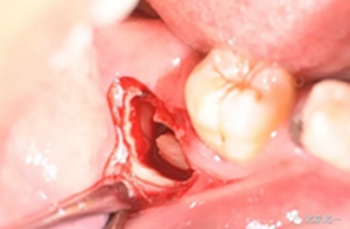

第二步:拔牙

切口設(shè)計關(guān)鍵點偏頰側(cè)。

去骨:原則暴露最大周徑線即可, 盡可能少去骨, 微創(chuàng)拔除。

截冠:有絲分裂至關(guān)重要。 保證微創(chuàng)下拔除智齒。